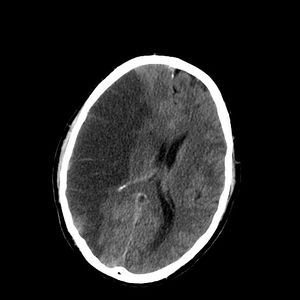

A CT showing early signs of a middle cerebral artery stroke with loss of definition of the gyri and grey white boundary